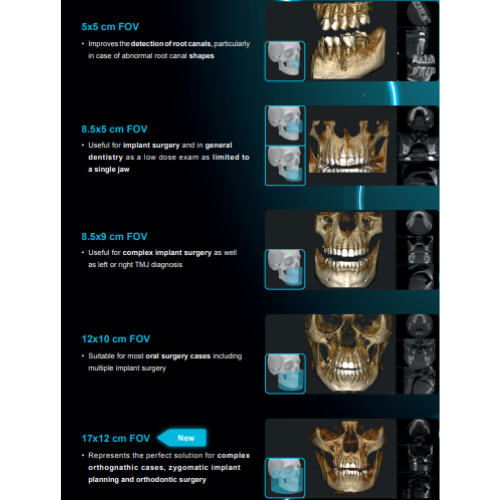

- Field Of View: 5x5, 8.5x5, 8.5x9, 12x10

- 2D and 3D Imaging

- Multi FOV

- Adjustable FOV

- Focused FOV

- Large FOV